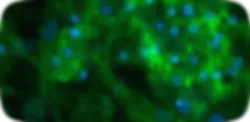

Cholestasis

Bile Canaliculi Loss

Hoechst (Nuclei) Phalloidin (Actin)